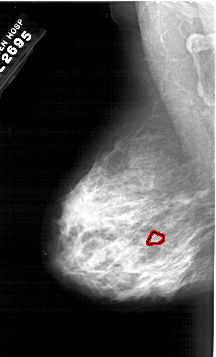

A_1983_1.LEFT_CC

LEFT_CC LINES 6436 PIXELS_PER_LINE 3811 BITS_PER_PIXEL 12 RESOLUTION 43.5 OVERLAY

FILE: A_1983_1.LEFT_CC.OVERLAY

TOTAL_ABNORMALITIES 1

ABNORMALITY 1

LESION_TYPE CALCIFICATION TYPE PUNCTATE DISTRIBUTION CLUSTERED

ASSESSMENT 4

SUBTLETY 1

PATHOLOGY MALIGNANT

TOTAL_OUTLINES 1

BOUNDARY